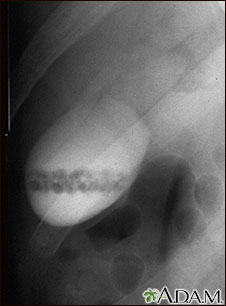

Colecistograma de un paciente con cálculos biliares.